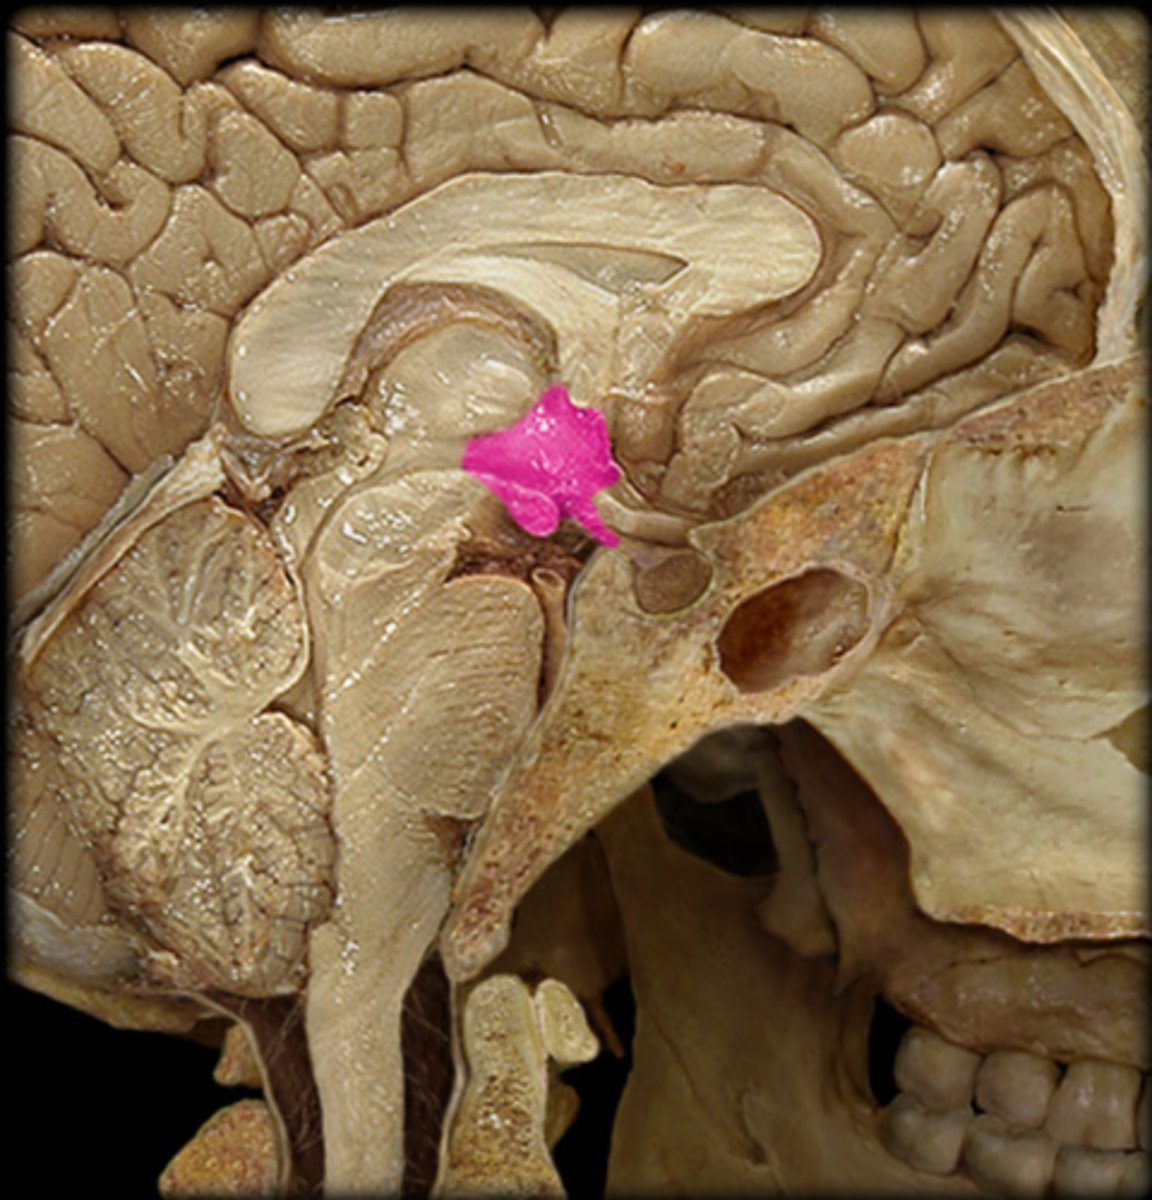

Hypothalamus and Pineal Gland Anatomy & Physiology II Lab (Hypothalamus & Pineal Gland: Dissection & Notes) Endocrine System

pineal gland

What hormone is produced in the pineal gland?

melatonin

Hormone of the Pineal Gland

Makes us drowsy and regulates our sleep-awake cycle called the circadian rhythm. Production increases during periods of darkness and decreases with increased light.

epithalamus

The pineal gland is located in the ________________.

pineal sand

The pineal gland has an important role in radiology due to the presence of a radioplaque substance called ____________ ____________. This provides radiologists with an easily distinguished landmark.